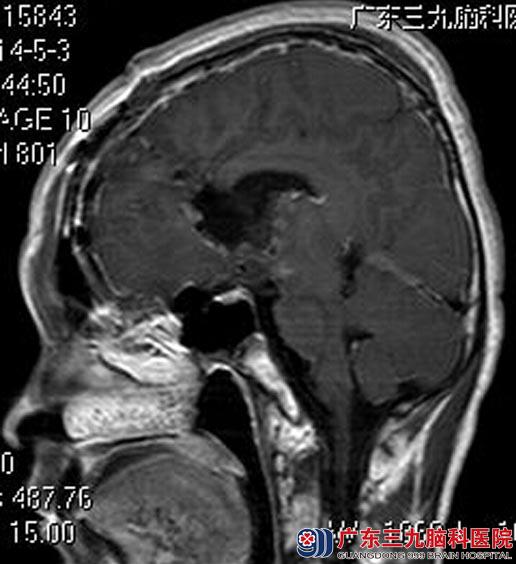

完善相关检查后,鲁明主任主刀,在全麻下行左侧额叶、脑室内肿瘤切除术,术中见灰白色肿瘤组织,质软,血供丰富,予超声刀逐步切除肿瘤,手术顺利。术后病理结果:生殖细胞瘤。

▲术后